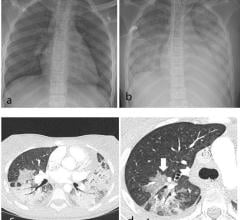

October 6, 2020 — According to an open-access article in ARRS’ American Journal of Roentgenology (AJR), dual-energy ...

September 30, 2020 — Newly released study results present a strong case for lung cancer screening in New Zealand — ...